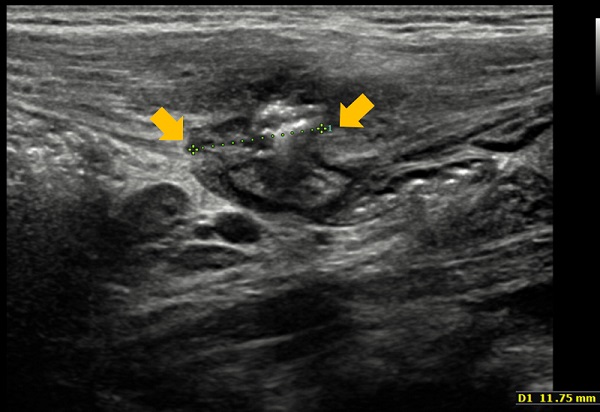

Ante la sospecha de hernia de Spiegel, se pide nueva ecografía orientada, que confirma el diagnóstico (Fig. 1 y Fig. 2).

La ecografía abdominal, prueba complementaria que confirma el diagnóstico, no está exenta de dificultades, debido a que la masa es evanescente. El interior del saco herniario puede estar vacío, pero también puede contener asas intestinales o el testículo ipsilateral, cuando se asocia a criptorquidia. La ecografía Doppler valora si hay estructuras vasculares implicadas.